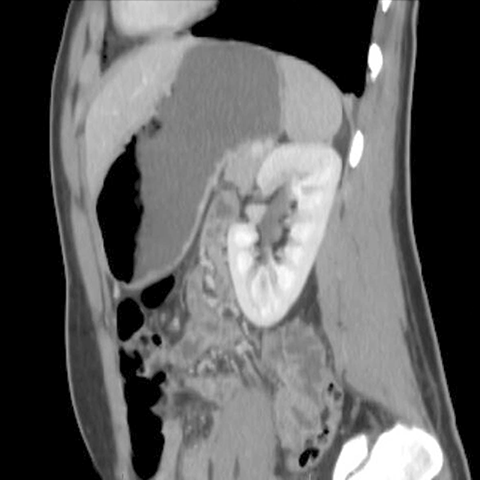

Normal kidneys, CT [8 of 9]